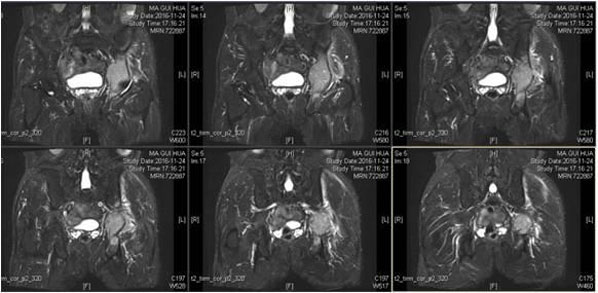

术前检查

术前3D打印模拟 术前模拟假体置入 术前3D打印的金属假体模型